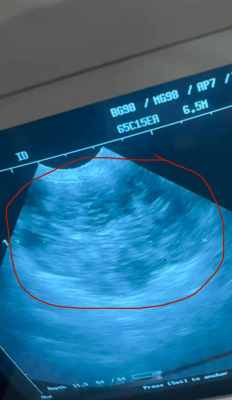

У нас опять горе, опять беда. Мы - большой Машкинский муниципальный приют. Куча собак, непрерывная битва за жизнь, беда за бедой... Думаю, кто нас знает, видит наши непрерывные катастрофы. Знает, что мы совсем уже, абсолютно безденежны и выжаты. А сейчас, вот. Тихая, не очень ручная, так и не нашедшая хозяина старушка Галочка. Как могла, жила в приюте, бегала гулять, ела, а потом как- то начала увядать. Похудела, начала хуже есть, перестала брать угощения, ну что, начали с УЗИ. А там ОГРОМНАЯ Опухоль на селезенке. Врач сказала, прямо очень большая, настолько большая, что может рвануть в любой момент. От резкого движения, от удара, просто побежит на выгул и опухоль рванет. Доктор делала УЗИ, тыкала нас носом в экран и так монотонно говорила, что надо срочно оперировать, не затягивайте, счет на дни...., а мы с ужасом понимали, что после операции Офелии и гибели в клинике нашего любимого Портоса мы еще за них не расплатились, а тут новая беда. Администратор, это она на видео говорит, просто плачет. Она боится, что пока мы что - то наберем, опухоль лопнет и Галочка погибнет у нас всех, бессильных, на глазах. Жалко ее безумно. Невозможно смотреть в ее седую морду, эти уже забеленные катарактой глаза и понимать, что вот она умирает, а мы не можем заплатить за ее жизнь. Ужасная, страшная обыденность...